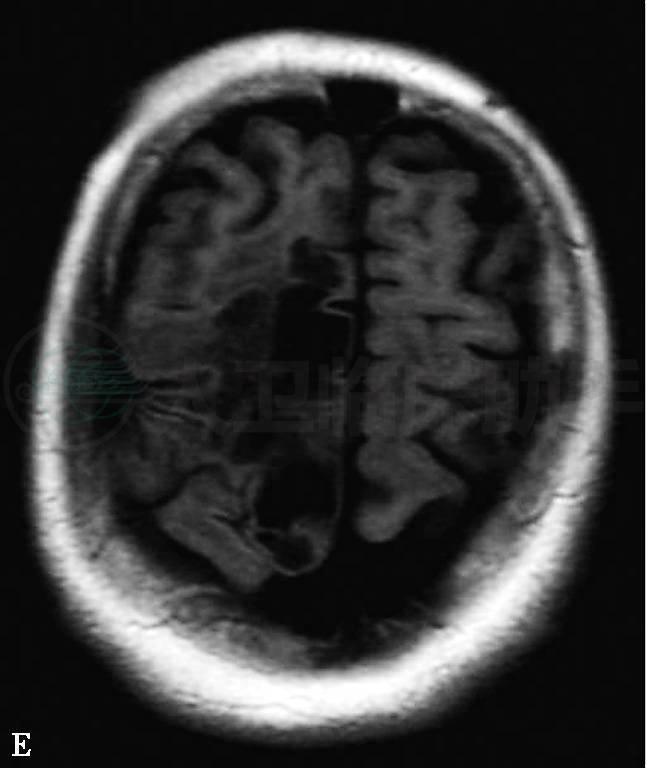

2004年10月11日拟开始用青霉胺治疗,因出现严重泌尿系感染伴腹胀呕吐及癫痫再发而暂缓,给予对症治疗。10月18日复查头颅MRI:脑干、桥小脑脚、双侧基底节区、双侧放射冠及半卵圆中心和外囊区可见片状异常信号,T1WI稍低信号,T2WI、T2FLAIR、DWI呈高信号;右额叶可见囊性异常信号T2WI呈高信号、T1WI及DWI呈低信号,与脑脊液相似(图1)。与入院前MRI片比较有进展。

图1 2004年10月18日头颅MRI:(A-D)T2WI像显示:(A)中脑斑片状稍高信号影,边界模糊;(B)中脑“熊猫脸”征;(C)双侧丘脑及豆状核对称性高信号;(D)双侧壳核对称性条状高信号